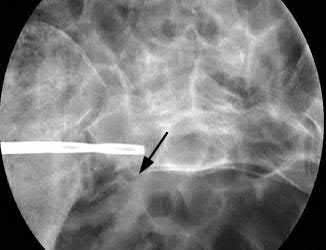

A 12-year-old obese boy presents with vague left thigh and knee pain. He is diagnosed with a Slipped Capital Femoral Epiphysis (SCFE) as seen in similar clinical scenarios.

During percutaneous in-situ fixation, unrecognized penetration of the guide wire into the hip joint occurs. What is the most likely specific complication resulting from this technical error?

Explanation

Chondrolysis is a severe complication of SCFE characterized by rapid destruction of the articular cartilage. While it can occur idiopathically, its most established iatrogenic cause is unrecognized intra-articular hardware penetration. The 'approach-withdraw' fluoroscopic technique is required during pinning to assure pins are entirely intraosseous. Avascular necrosis (AVN) is usually due to damage to the epiphyseal blood supply (retinacular vessels) secondary to the initial displacement, forceful closed reduction, or posterosuperior pin placement.